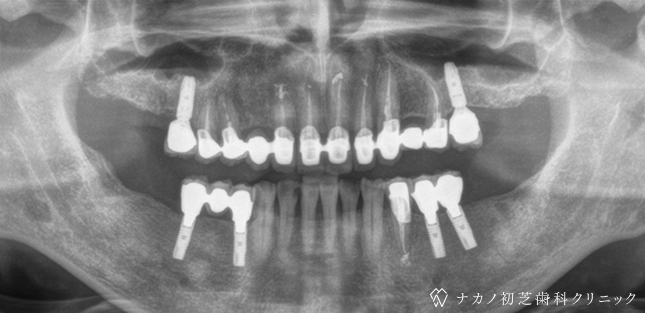

インプラント・7本 (70代男性)

BEFORE

AFTER

年齢 70代男性

治療内容 インプラント治療7本(骨造成の併用)

インプラント治療とは、歯を抜いた所にチタン製の人工歯根を埋入し、その上に歯を入れる方法です。骨を増やすことで、より審美的に治療が出来ました。費用 1本 400,000円(税込 440,000円)

リスク・副作用

腫れ・疼痛・違和感を感じるなどの症状を生じることがあります。